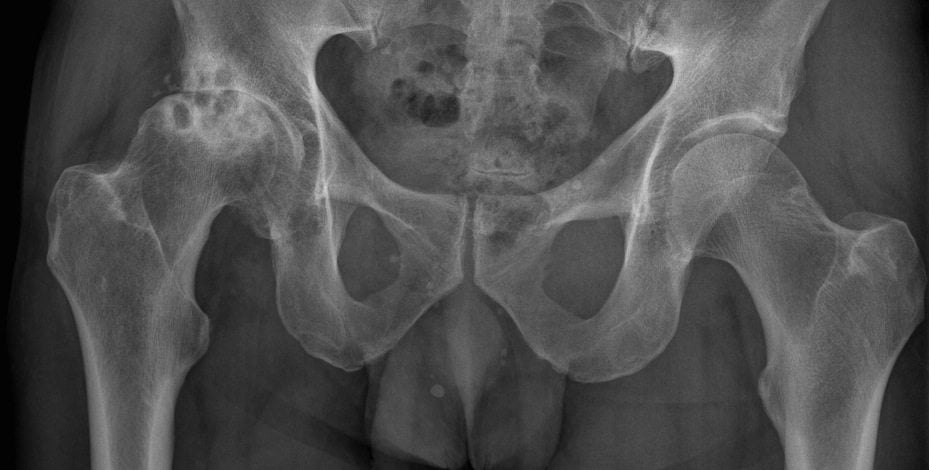

- рентгенография.

По результатам исследований врач установит изменения, которые характерны для каждой отдельной стадии протекания коксартроза. Также доктору нужно собрать анамнез жизни пациента и его симптоматику.